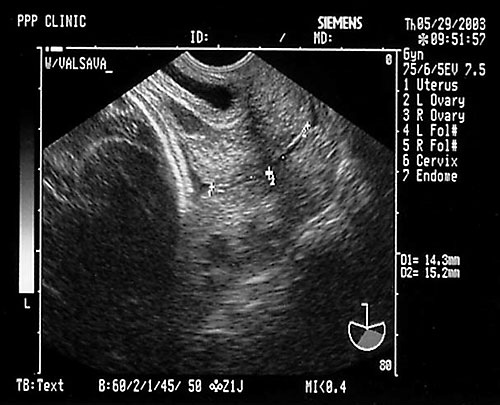

Normal appearing cervix. Closed and long.

Length cervical canal

10-50 mm in 2nd and 3rd trimesters

50th% is 3.5 cm

10th% is 2.5 cm

90th% is 4.5 cm

- Cervical length < 2.5 cm at 22-24 weeks 6x increase in PTB before 35 weeks.